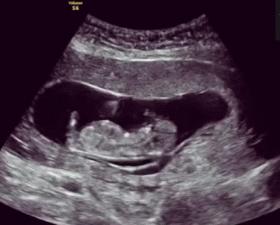

孕早期除了孕吐反应,准妈妈很难知道胎儿在宫内的状态。但从16周开始,准妈妈逐渐感受到胎动,就能时刻知道宝宝在干嘛啦!

准妈妈可以在16-20周感觉到首次胎动,但由于个体感觉、腹壁厚度、胎盘位置不同,感受到胎动的时间也千差万别。有的准妈妈18周没感觉到胎动就以为胎儿有问题,其实大可不必,胎儿一直在动,只不过身体太小,有羊水缓冲,准妈妈感觉不到。而且,第一胎的准妈妈在20周才可以感觉到胎动。这时的胎动也很微弱,有人说像蝴蝶在扇动翅膀,有人说像小鱼吐泡泡,很微弱,需要仔细感觉才能感到。到了孕中期,大约在32周时胎动达到强度和频率的高峰,并且逐渐有规律性了。孕晚期胎动因羊水相对减少和空间减小在形式上会有些变化,但是胎动的次数一般不明显减少。